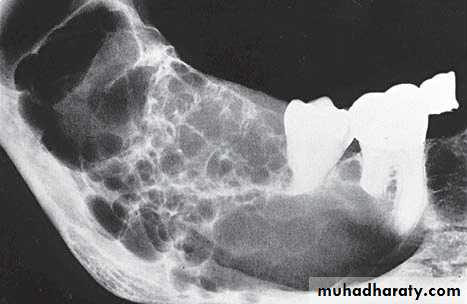

Large multilocular aneurysmal bone cyst

in the ramus with marked expansion andthe displacement of/8.

It is non-neoplastic ,exaggerated , localized, proliferative lesion of vascular tissue, containing giant cells.

It’s a variation of the central giant cell granuloma , can be diagnosed only by histological examination